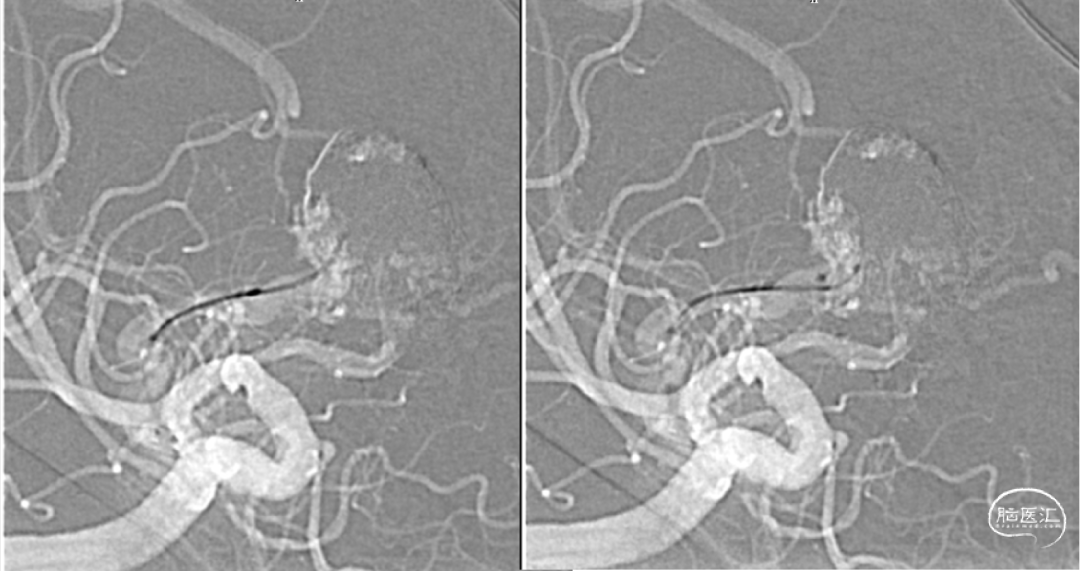

经静脉入路超选到位

经Echlon10微导管填入弹簧圈做塞子

经Apllo微导管注入Onyx胶